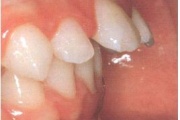

Vali sind huvitav pilt ja me näitame sellega seotud haigust ja sümptomeid